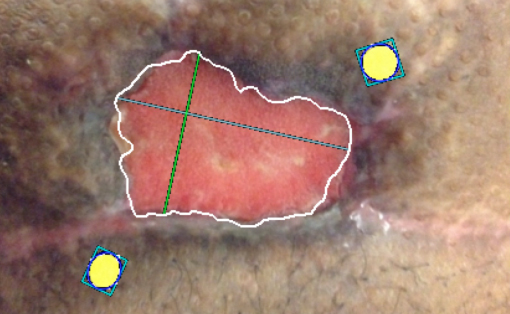

July 16, 2018 -Leveraging the principle of fluorescence, MolecuLight i:X emits a safe violet light which causes bacteria ≥ 104 CFU/g to fluoresce Read More